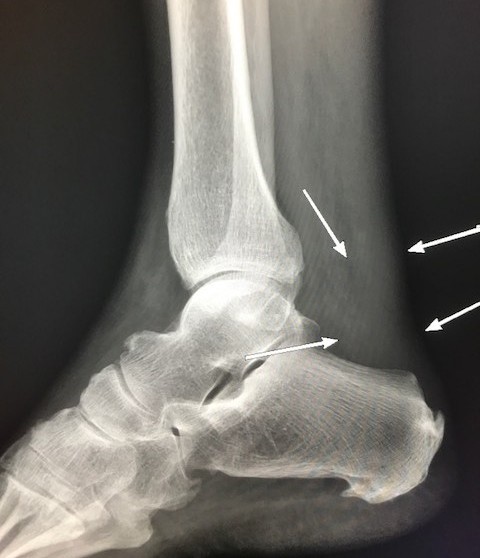

4.X-ray Film:

A plain X-ray film may identify problems with the bones or ankle joint, but it cannot diagnose Achilles tendon problems.